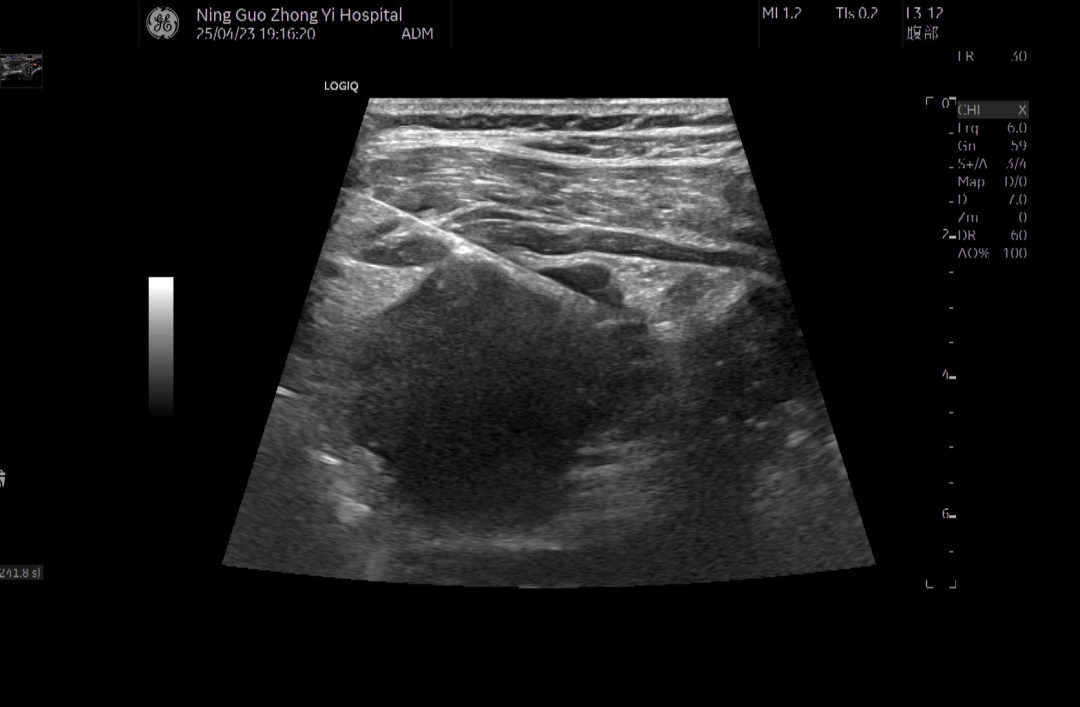

近期我院超声科迎来一例怀疑肠道肿瘤肝转移的患者,为明确病理,行腹腔内肠道周边肿块穿刺活检,经一番穿刺术前检查后,在超声实时监视引导下经皮经腹腔,穿刺针精准到达肿块边缘,击发成功,取得满意组织条,术中无明显出血,术后加压包扎,密切观测生命体征,无并发症。病理报告腺癌,明确了诊断,为下一步治疗指明方向。 近期超声科也遇到一例外周肺实变的患者,为明确病理,行实变肺组织穿刺活检,经一番穿刺术前检查后,在超声实时监视引导下经皮经胸腔,穿刺针精准到达实变肺组织内,击发成功,取得满意组织条,术中无明显出血,术后密切观测生命体征,无并发症。病理报告显示实变肺组织为炎性组织,明确了诊断,确定了治疗方向,取得满意效果。去年超声科对一位周围型肺肿块患者也在超声实时监视引导下经皮经胸腔行肿块穿刺活检,做了病理和免疫组化检测,明确诊断为肺腺癌,为治疗方案提高了依据。 我院超声科超声介入从过去的甲状腺、乳腺结节以及浅表淋巴结穿刺活检到如今的胸腹腔脏器肿块的穿刺活检是一个技术不断进步不断成熟发展的飞跃。超声科将不断提升实力,精准高效的服务好病患。 |